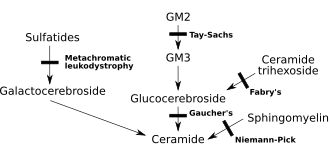

Метахромати́ческая лейкодистрофи́я (англ. Metachromatic leukodystrophy (MLD), также сульфати́дный липидо́з) — редкое наследственное заболевание из группы лизосомных болезней накопления с аутосомно-рецессивным механизмом наследования нарушения обмена веществ[1]. Данная нозологическая единица из разряда лейкодистрофий (патология роста и/или развития миелиновой оболочки, покрывающей большинство нервных волокон центральной и периферической нервной системы) относится к сфинголипидозам. Характеризуется недостаточностью арилсульфатазы А[2] (цереброзидсульфатазы) — фермента лизосом, участвующего в метаболизме сфинголипидов, что вызывает накопление цереброзида сульфата[1][3].

Патогенез

Метахроматическая лейкодистрофия развивается в результате дефицита лизосомного фермента арилсульфатазы А (АРСА, англ. ARSA)[2] или цереброзидсульфатазы. На фоне развёртывания клинической симптоматики уровень активности фермента в лейкоцитах существенно снижается и составляет менее 10 % от нормальных величин[6]. Тем не менее, одного анализа активности цереброзидсульфатазы недостаточно для верификации диагноза. Описана форма псевдо дефицита АРСА (англ. ARSA pseudo deficiency), при которой активность фермента составляет от 5 до 20 % от нормы и при этом отсутствуют признаки метахроматической лейкодистрофии[6]. На фоне дефицита или недостаточности фермента происходит накопление сульфатида во многих тканях организма, что в конечном счёте приводит к разрушению миелиновой оболочки нервных волокон. Миелиновая оболочка — липидное покрытие нервного волокна, которое не только защищает его, но и способствует повышению скорости проведения импульса по нерву. Потеря миелина центральной нервной системой (мозг) и периферической нервной системой нарушает систему контроля и снижает мобильность мышц, таким образом нарушая их функцию.

Арилсульфатаза А (англ. Arylsulfatase A, ARSA) активируется сапозином Б (англ. Saposin B, Sap B) — не ферментативным белковым кофактором. Таким образом, в случае определения накопления сульфатида на фоне нормального уровня арилсульфатазы А, причиной развития метахроматической лейкодистрофии станет не дефицит фермента, а его низкая активность в результате недостаточности сапозина Б. Неактивированный фермент не может достичь нормального уровня эффективности, что в конечном итоге ведёт к накоплению сульфатида, развитию клинической картины и прогрессированию заболевания. Следует отметить, что частота данной патологии значительно ниже, чем традиционной метахроматической лейкодистрофии[7].